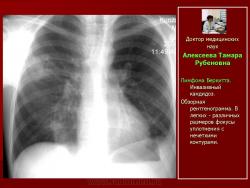

Рис. 13. Б-ной К. Лимфома Беркитта. Инвазивный кандидоз.

Обзорная рентгенограмма. В легких - различных размеров фокусы уплотнения с нечеткими контурами.

Рис. 14. Тот же б-ной К. Лимфома Беркитта. Инвазивный кандидоз

Компьютерные томограммы. Субплеврально расположенные треугольной формы фокусы уплотнения неоднородной структуры.